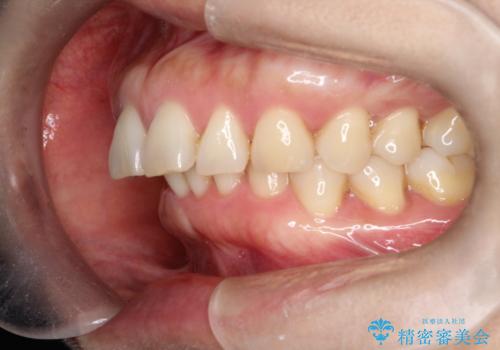

【インビザライン】出っ歯を治したい

- 前歯が出ていることを主訴に来院されました。

インビザラインにて臼歯部の遠心移動及びIPRを行なっています。

叢生量が多いケースでしたが、綺麗な歯並びとなり患者様にも満足していただきました。